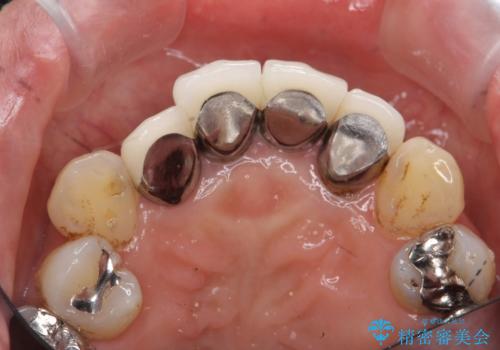

以前に治療した前歯クラウンは月日が経過することで劣化・歯肉の位置変化を引き起こし審美障害を引き起こしています。

劣化したクラウンを除去し、再発した虫歯を徹底的に除去したのち根管治療・ファイバーコア築盛を行いジルコニアクラウン製作へと移ります。